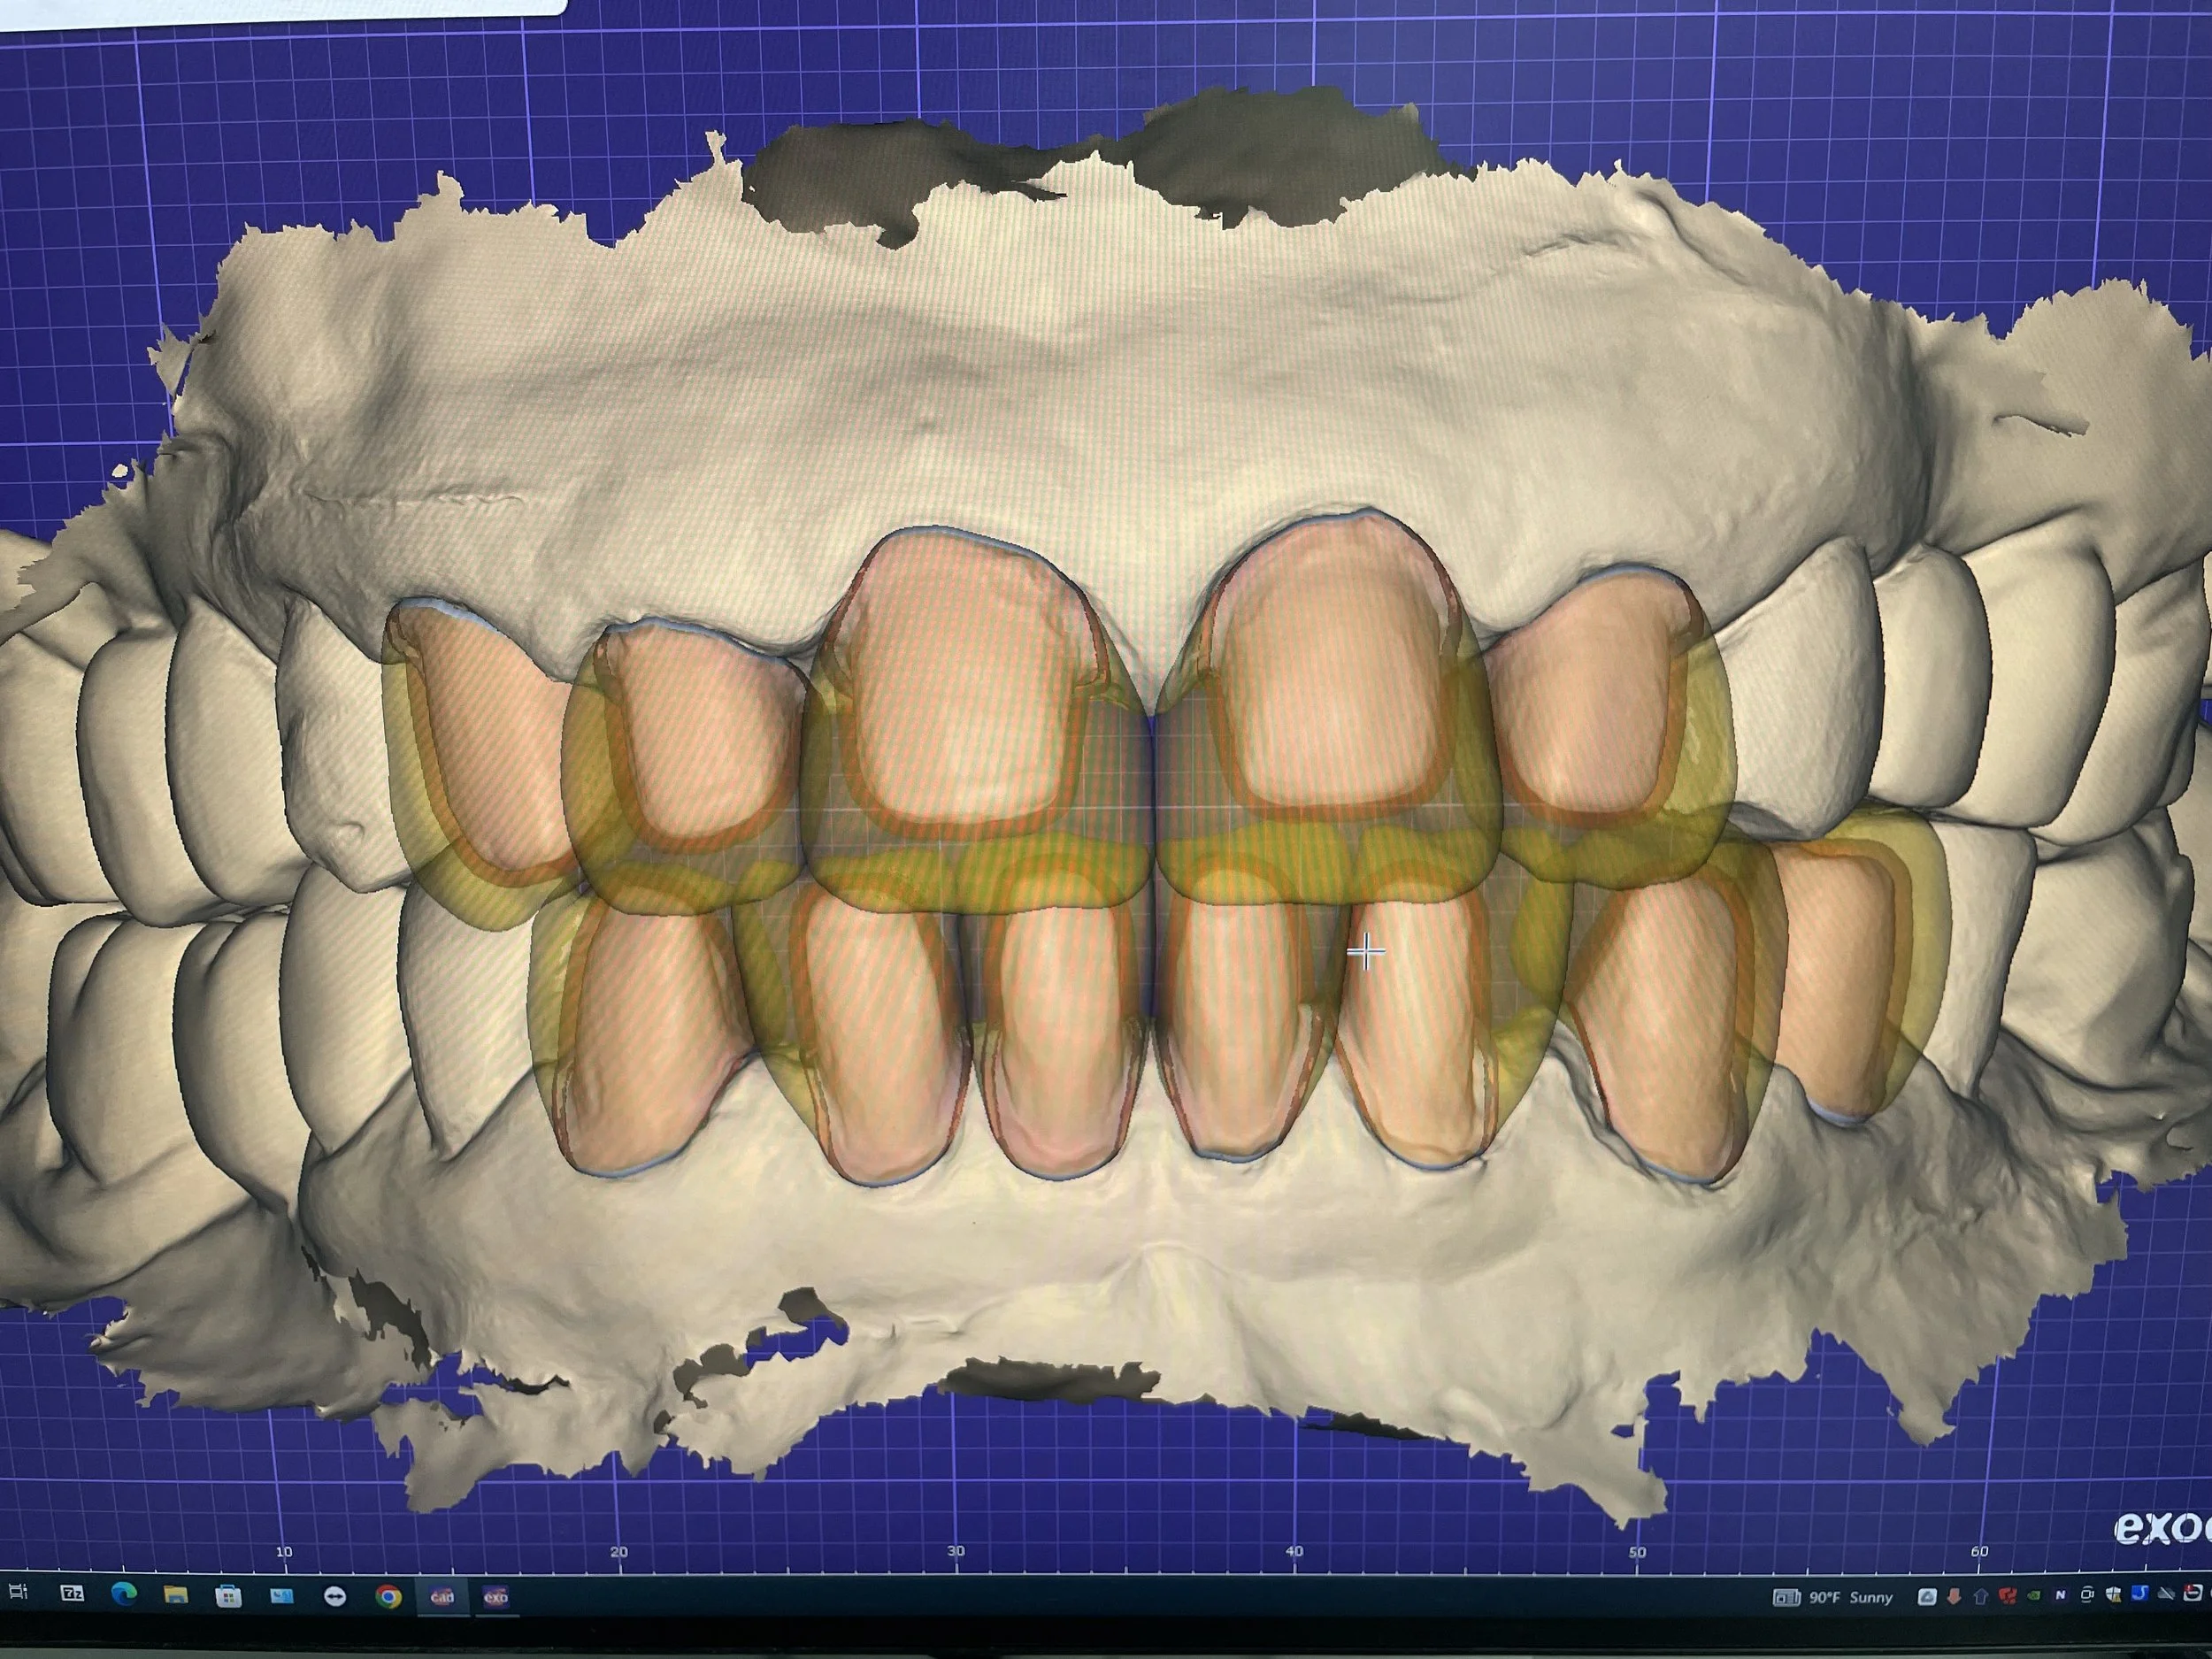

Advantages of Digital Dentistry

Superior Accuracy & Predictable Results

With precise 3D scans and CAD/CAM-designed prosthetics, treatments fit perfectly the first time—reducing remakes and speeding up patient care.

Streamlined Workflow & Consistent Quality Errors

Our digital processes replace traditional manual steps, helping to minimize mistakes and save time in both treatment planning and prosthetic fabrication, while precision technology ensures high-quality, predictable restorations.